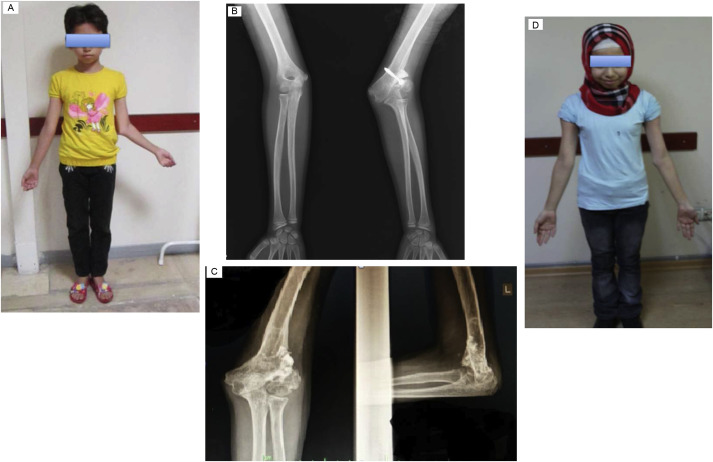

Regarding complications, there were 2 grade 1 pin tract infections treated with appropriate dressing and oral antibiotic, and 1 diaphyseal fracture of humerus at proximal Schanz screw insertion caused by forceful manipulation during physiotherapy after removal of fixator. Circular external fixator was reapplied until solid union of fracture was achieved. No neurovascular complications occurred. Functional outcome was rated excellent in 7 patients, and good in 1 patient. Clinical and radiographic views of 2 patients each treated for cubitus varus and valgus deformity are provided in Fig. 2 ; Fig. 3 , respectively.

|

Fig. 3. Eleven-year-old girl with cubitus valgus deformity (patient #6). (a) Clinical appearance. (b) Anteroposterior radiography before correction. (c) Anteroposterior and lateral radiographs at last follow-up. (d) Clinical appearance at last follow-up. |